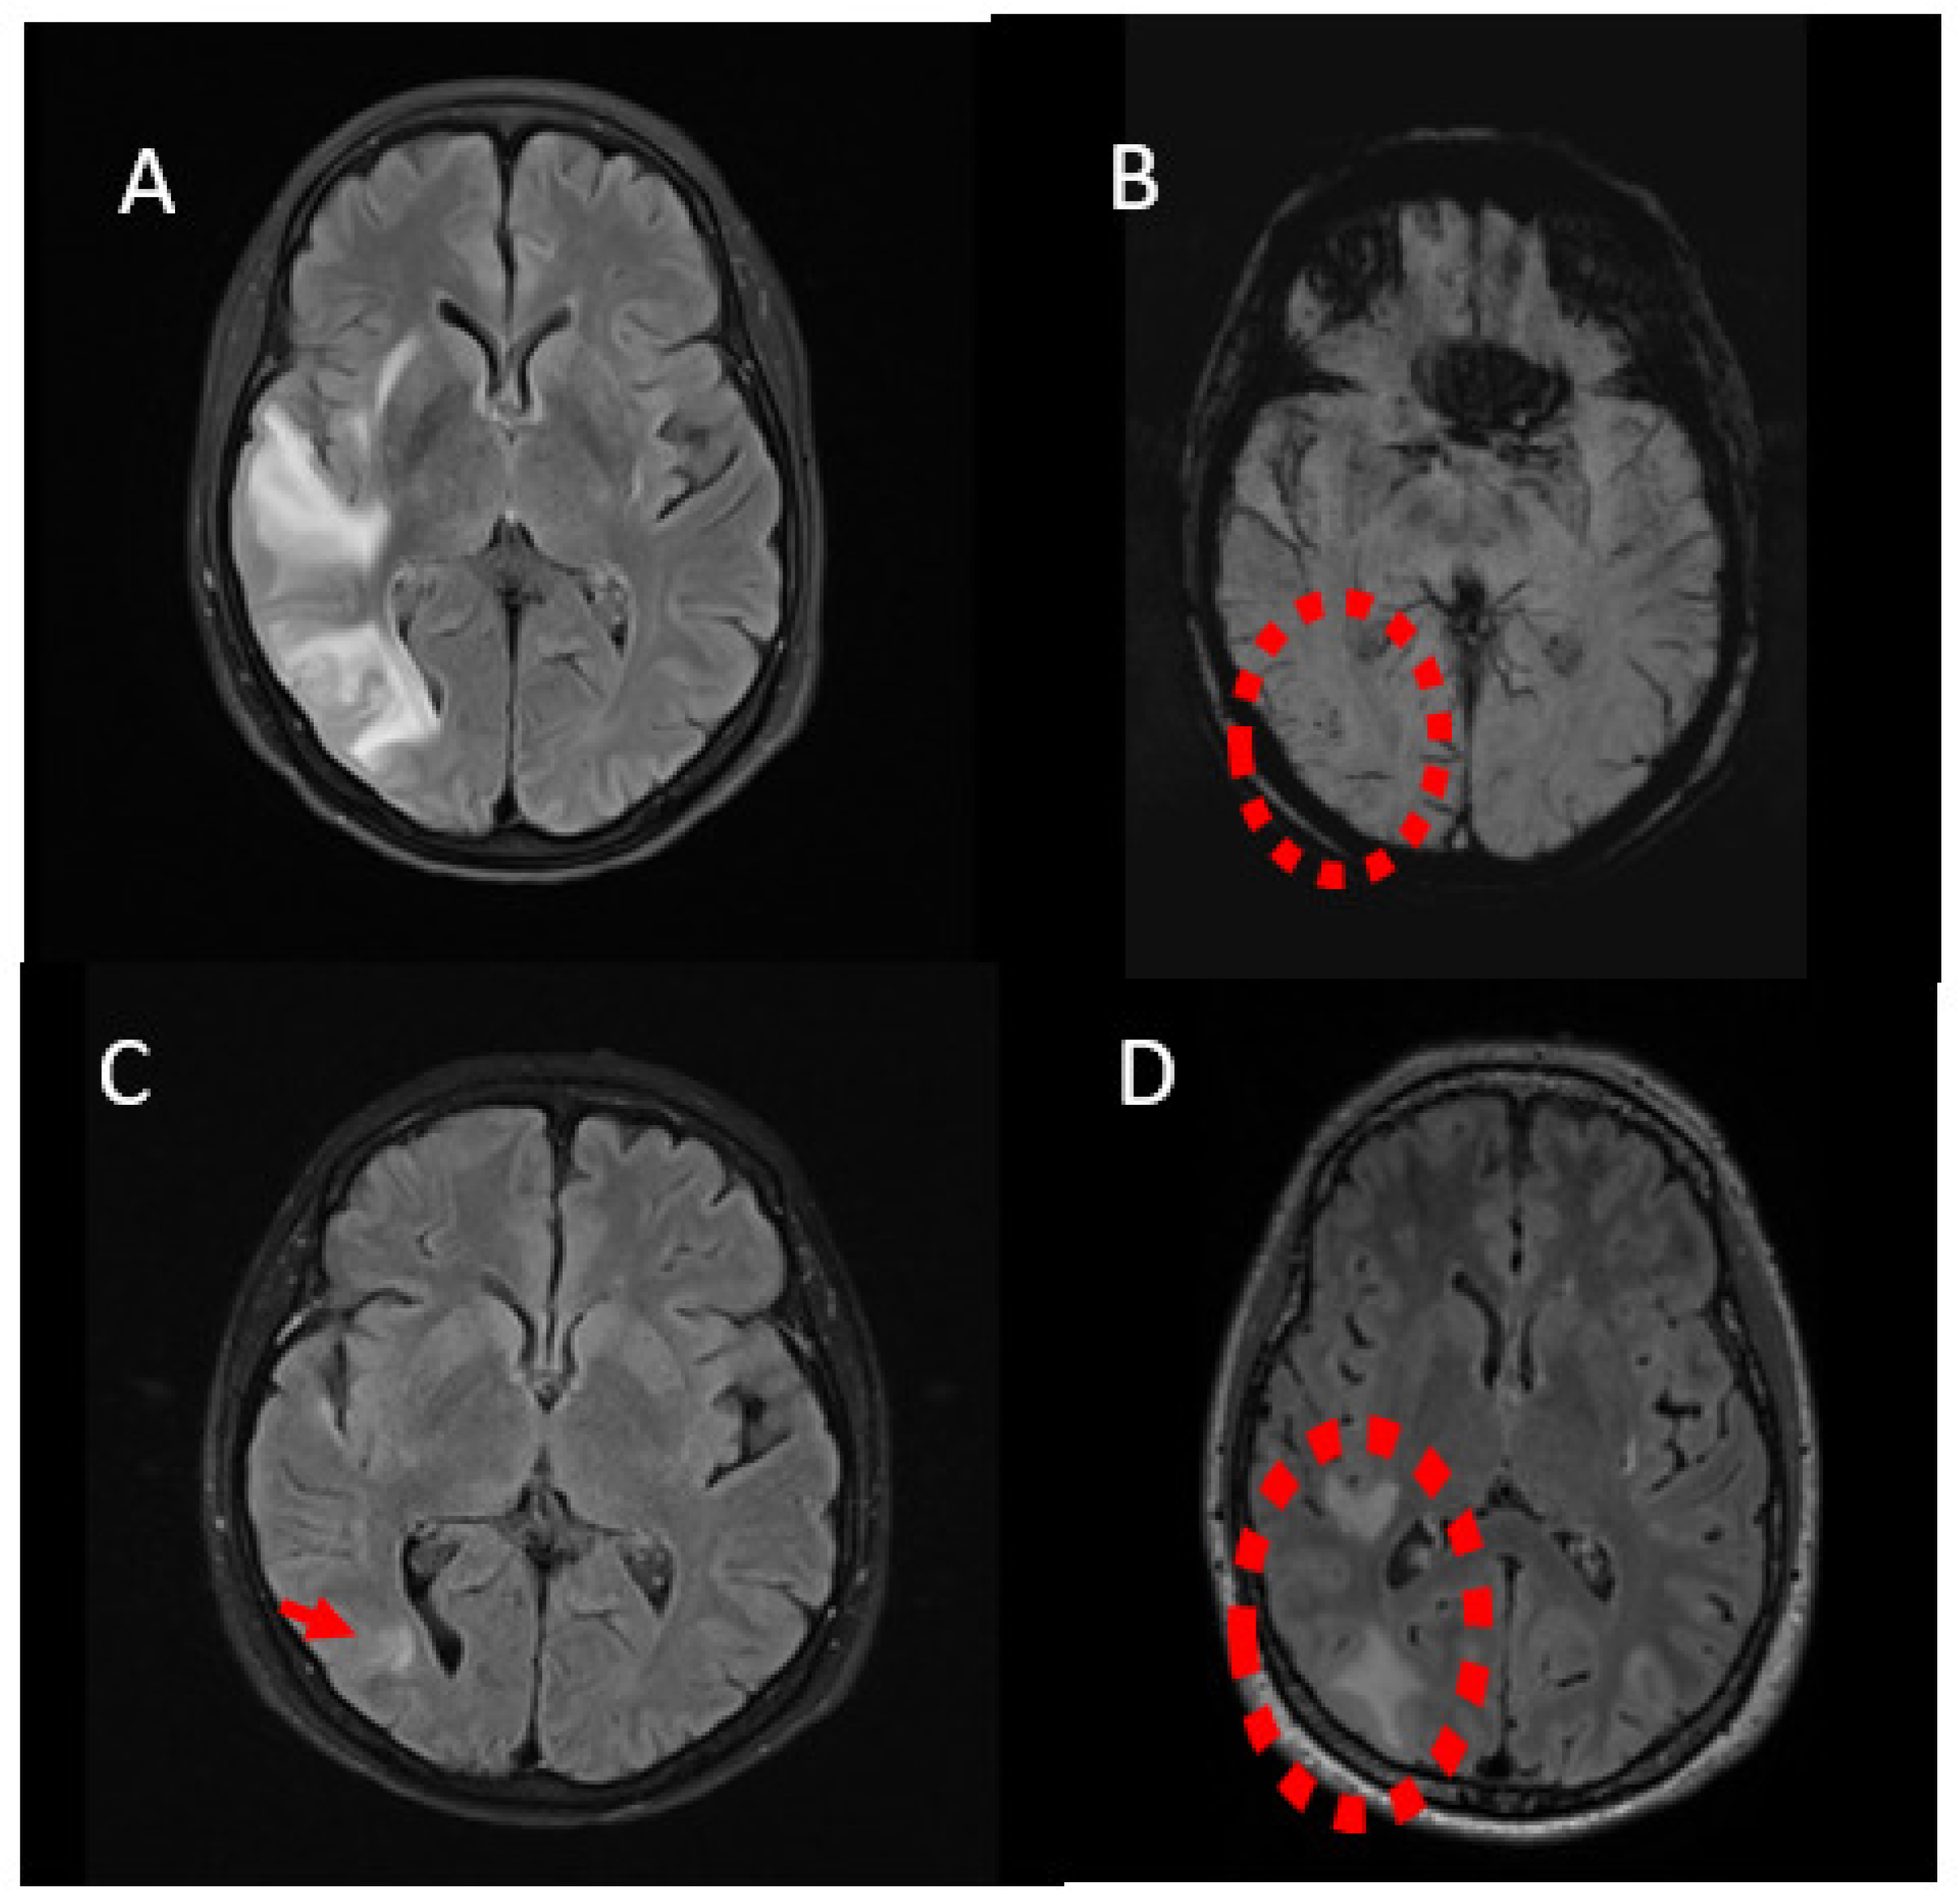

| Case 1 * F/64 | Endovascular coiling/ right PCom | 12 months | headache, auditory hallucinations, paresthesias and weakness of the left upper limb | Enhancing lesions, vasogenic edema, low SWI signals | No | Steroids **/Initial improvement, recurrence after tapering | 3.5 years |

| Case 2 F/62 | Endovascular coiling/ right PCom | 6 months | left homonymous hemianopsia, left-sided hemiparesis, auditory hallucinations and seizures | Enhancing lesions, vasogenic edema, low SWI signals | No | Steroids **/improvement | 3 years |